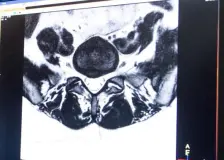

Londýn - Chirurg z Londýna provedl první robotickou operaci na dálku v Británii, pacient se při ní nacházel 2400 kilometrů daleko na Gibraltaru. Operace, při níž byla pacientovi odstraněna prostata,...